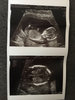

Ja tez już po prenatalnych wszystko jest w pozadku maluch ma 7,86 cm długości wiercił się ale płci nie znam niestety.

IMG_0762.JPG